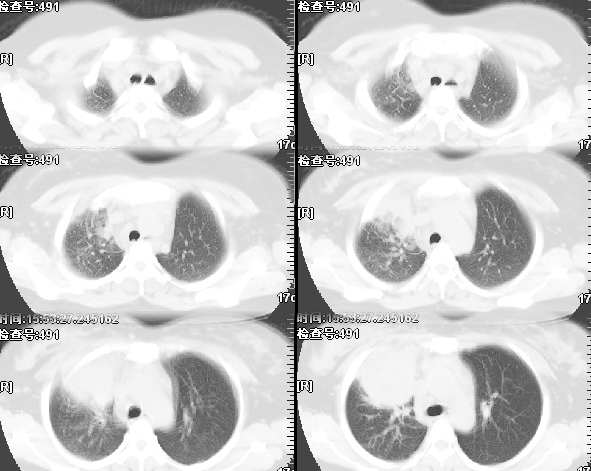

女,28岁咳嗽无痰偶有低烧,化验:白细胞1万零7,血沉正常

图象不错,无肺窗。右肺上叶前段支气管呈鼠尾样,边缘尚光滑,气管前淋巴结肿大,未见空气支气管征考虑占位性病变可能。与大叶性肺炎和早期肺脓肿鉴别,建议抗炎后复查。

右肺上叶前段与中叶见较大团块影。边界较清晰,纵隔隆突前淋巴结增大。考虑1肺部间叶组织肿瘤可能。2感染性病变

我觉得不要把患者年龄作为轻易排除肺癌的依据,病变呈大块状软组织密度,右肺中叶支气管可见中断,右侧肺门增大,要高度警惕肺癌,支气管镜应该能够给出正确的诊断。间质来源的恶性肿瘤尽管可以考虑到,但是从发病率上来说不首先考虑。

补充病例结果是:肺间变大t细胞淋巴瘤. 非霍奇金淋巴瘤(间变大t细胞性)iv期bipi 2分

右肺中下叶切除